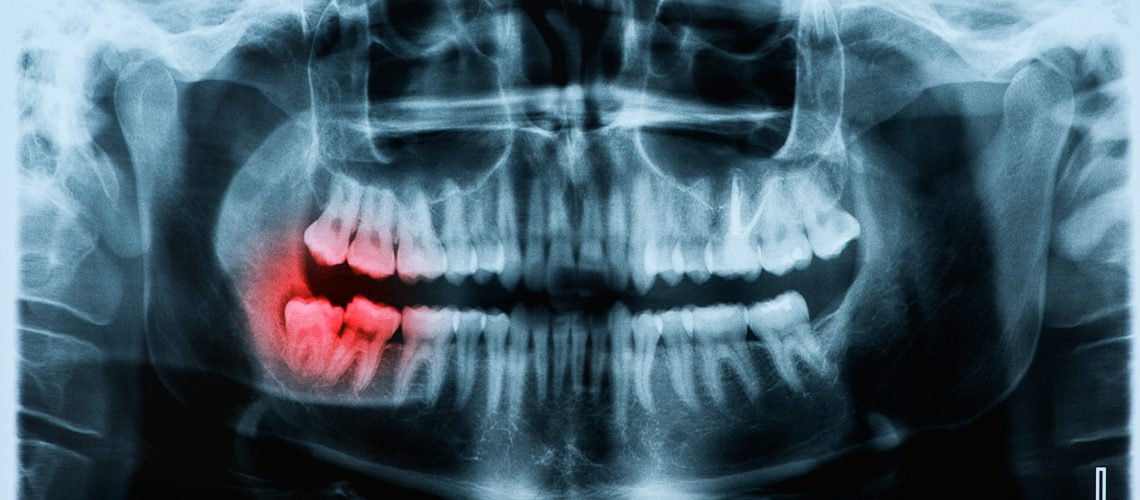

Panoramic x-ray image of teeth and mouth with wisdom teeth